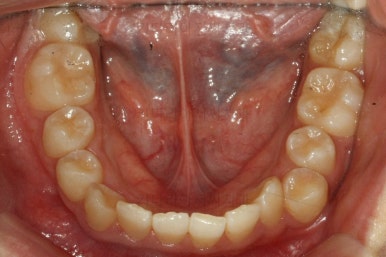

치료 10개월째의 모습입니다.

이정도면 다 끝난 것 같은 느낌이 드시지 않나요? 과개교합도 개선시켰고 매복치아 덧니도 가지런하게 했어요.

작은 앞니가 왜소치이다 보니 윗니에는 틈이 남아있고 교합도 조금 엉성한 모습이에요.

왜소치의 사이즈가 위아래 교합을 맞춰주는데 방해가 된다고 판단하여 왜소치를 크게 해주기로 결정했습니다.

우선 현재 상태에서는 사이즈를 크게 하지 못하기 때문에 왜소치 좌우로 틈새를 만들어주기로 했습니다.

왜소치 좌우로 틈을 일부러 만든 상태입니다.